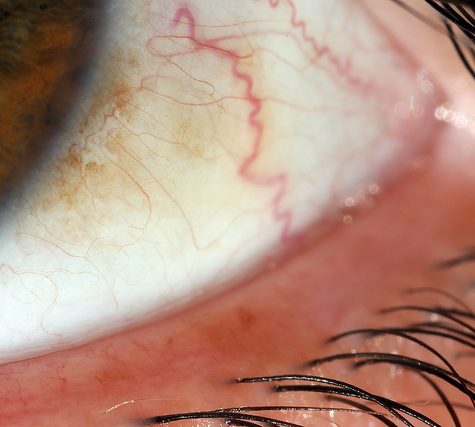

The sclera, also known as the white of the eye, is the opaque, fibrous, protective, outer layer of the eye containing mainly collagen and some elastic fiber.[2] In humans, the whole sclera is white, contrasting with the coloured iris, but in other mammals the visible part of the sclera matches the colour of the iris, so the white part does not normally show. In the development of the embryo, the sclera is derived from the neural crest.[3] In children, it is thinner and shows some of the underlying pigment, appearing slightly blue. In the elderly, fatty deposits on the sclera can make it appear slightly yellow.

The human eye is relatively rare for having an iris that is small enough for its position to be plainly visible against the sclera. This makes it easier for one individual to infer where another individual is looking, and the cooperative eye hypothesis suggests this has evolved as a method of nonverbal communication.

The sclera, also known as the white of the eye, is the opaque, fibrous, protective, outer layer of the eye containing mainly collagen and some elastic fiber.[2] In humans, the whole sclera is white, contrasting with the coloured iris, but in other mammals the visible part of the sclera matches the colour of the iris, so the white part does not normally show. In the development of the embryo, the sclera is derived from the neural crest.[3] In children, it is thinner and shows some of the underlying pigment, appearing slightly blue. In the elderly, fatty deposits on the sclera can make it appear slightly yellow.

The human eye is relatively rare for having an iris that is small enough for its position to be plainly visible against the sclera. This makes it easier for one individual to infer where another individual is looking, and the cooperative eye hypothesis suggests this has evolved as a method of nonverbal communication.